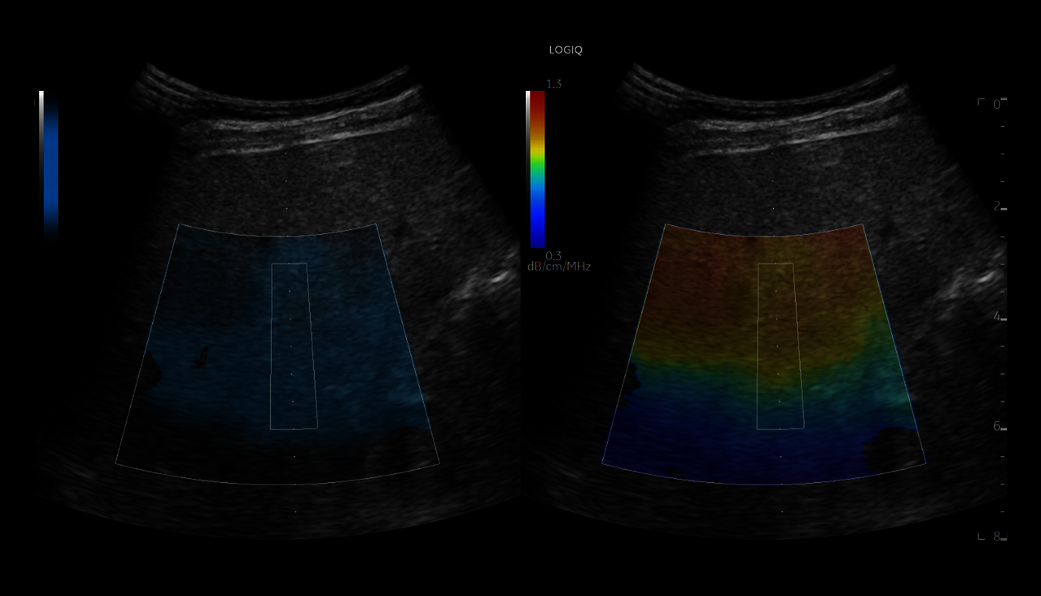

2D Shear Wave Elastography enables non-invasive 2D quantitative assessment of tissue stiffness

Contrast-Enhanced Imaging (CEUS) optimizes the balance between penetration and resolution for improved contrast sensitivity